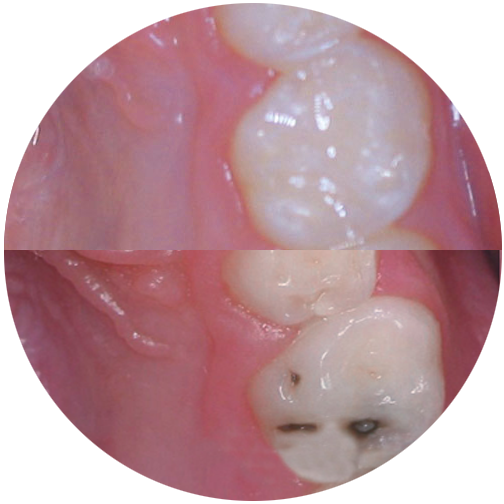

Wir machen ausschließlich weiße Füllungen. Dabei kann es sich um Komposite, Kompomere oder Glasionomerzemente handeln. Welches Material wo zum Einsatz kommt hängt von vielen Faktoren ab, die wir individuell mit Ihnen besprechen.

Bei Kompositen handelt es sich um hochwertige Kunststoffe, wie sie in der Erwachsenenbehandlung ebenfalls verwendet werden. Diese verwenden wir selbstverständlich bei allen bleibenden Zähnen sowie bei Milchzähnen, wenn er noch viele Jahre halten muss.

Kompomere sind eine Mischung aus den Kompositen und den Glasionomerzementen und kommen zum Einsatz, wenn eine hochwertige Füllung vorgesehen ist, es aber „schnell gehen muss“ aufgrund mangelnder Kooperation etwa. Diese Füllstoffe sind etwas weniger fehleranfällig aber fast genauso gut.

Glasionomerzemente eignen sich primär als Langzeitprovisorien, da sie nicht so langlebig sind wie Komposite.